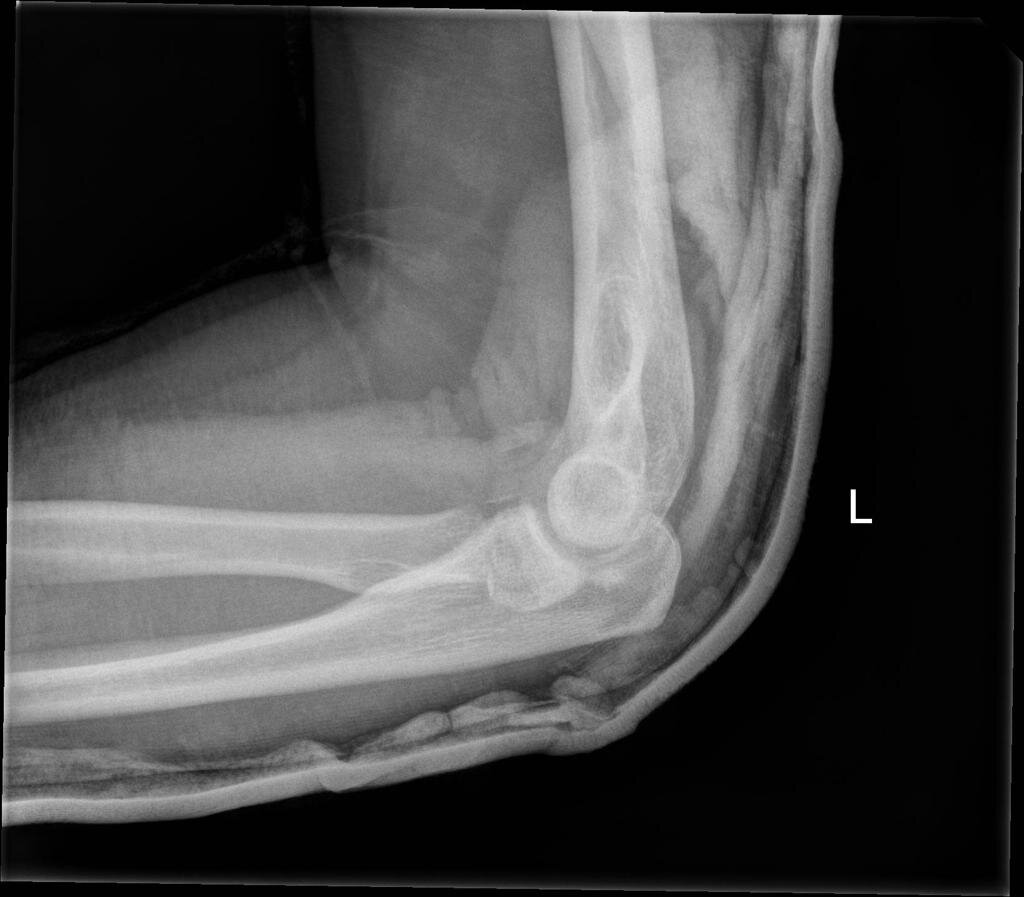

Figure 1: AP and lateral views of the left elbow. Author’s own images.

Plain radiography of the left elbow (Figure 1) shows a posterior elbow dislocation with tiny avulsion fractures from the posterior distal humerus.